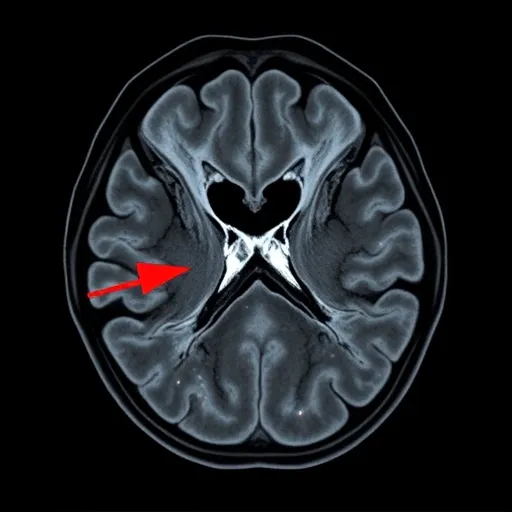

자기공명영상(MRI)은 반월상 연골판 파열을 진단하는 표준적인 비침습 검사 방법입니다. X-ray로는 보이지 않는 연골, 인대, 근육 등의 연부 조직 손상을 고해상도로 확인할 수 있습니다. MRI는 파열의 위치, 크기, 형태(수평, 방사상, 복합 등), 그리고 다른 인대(예: 십자인대)의 동반 손상 여부까지 파악할 수 있어, 수술이 필요하다면 수술 계획 수립에 결정적인 정보를 제공합니다. MRI 결과를 통해 연골 파열의 단계를 1~3등급으로 나누어 치료 방향을 설정합니다.

- 1-2등급: 연골 내부 변성 및 미세한 손상 단계로, 대부분 비수술적 치료(보존적 치료)를 시도합니다.

- 3등급: 연골판 표면까지 완전히 찢어진 파열 단계로, 통증과 잠김 증상이 동반될 경우 수술적 치료를 고려합니다.